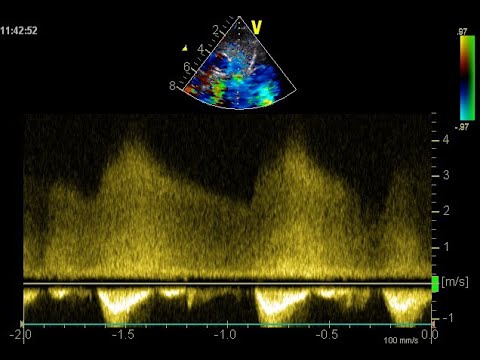

• Rôle des infirmiers en salle de cathétérisme - Fermeture de canal artériel prématuré

Rôle des infirmiers en salle de cathétérisme - Fermeture de canal artériel prématuré

Rôle des infirmiers en salle de cathétérisme - Fermeture de canal artériel prématuré thumbnail